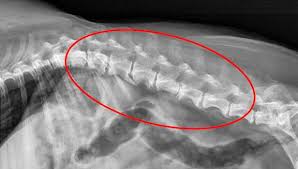

Symptoms of bone cancer in dogs. Does bone cancer in dogs spread quickly? It's a highly malignant and aggressive tumour, of which 75% is found in the legs of large and giant breed dogs. Diagnosis of arthritis in dogs. Bone cancer in dogs is rather common, with osteosarcoma as the most common type of bone tumor.

85% of bone cancer in dogs is a form called osteosarcoma.

20 Causes Of Lameness Limping In Dogs Walkerville Vet from www.walkervillevet.com.au It can grow in any of the bones in the body. When a dog's joint becomes arthritic, the cartilage becomes damaged, and the joint fluid becomes thin. Prevention of bone cancer several dog breeds are highly predisposed to developing osteosarcoma. The second type of bone cancer that manifests in dogs is quite rare and accounts to 5% of cancerous bone tumors. Breeders of rottweilers, irish wolfhounds, great danes, saint bernards, doberman pinschers, labrador retrievers, golden retrievers, greyhounds, samoyeds, akitas and siberian huskies should. Bones in a healthy joint have a smooth surface, which allows them to glide past each other when moving around. Bone cancer most commonly affects the long bones in the arms and legs. Neurological problems in older dogs.